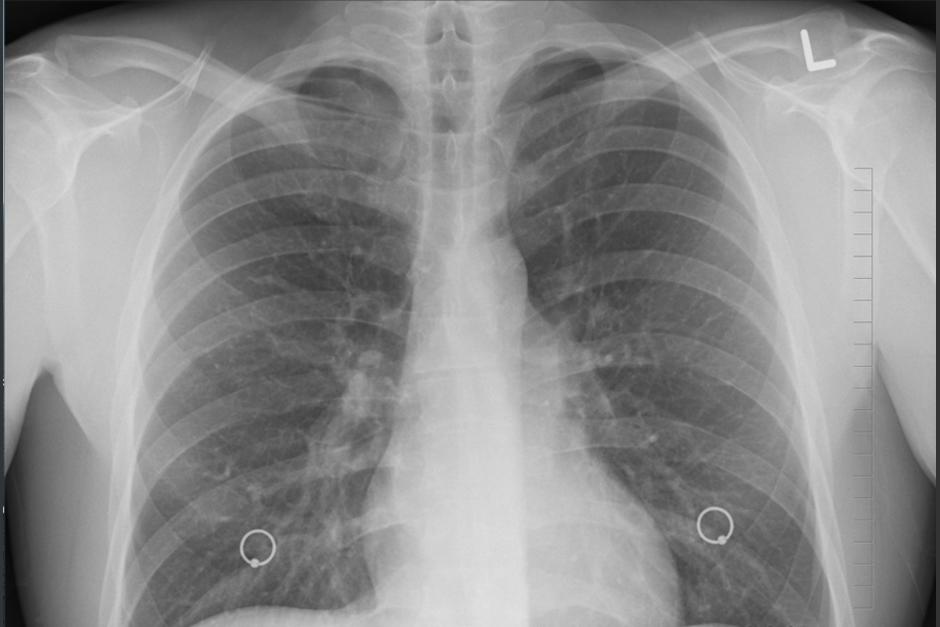

El cáncer de pulmón es considerado el más mortal en el mundo ya que causa más decesos anuales en comparación a los de mama, colon y próstata.

La mayoría de los pacientes de cáncer de pulmón, cerca del 80%, se diagnostican en estado avanzado.